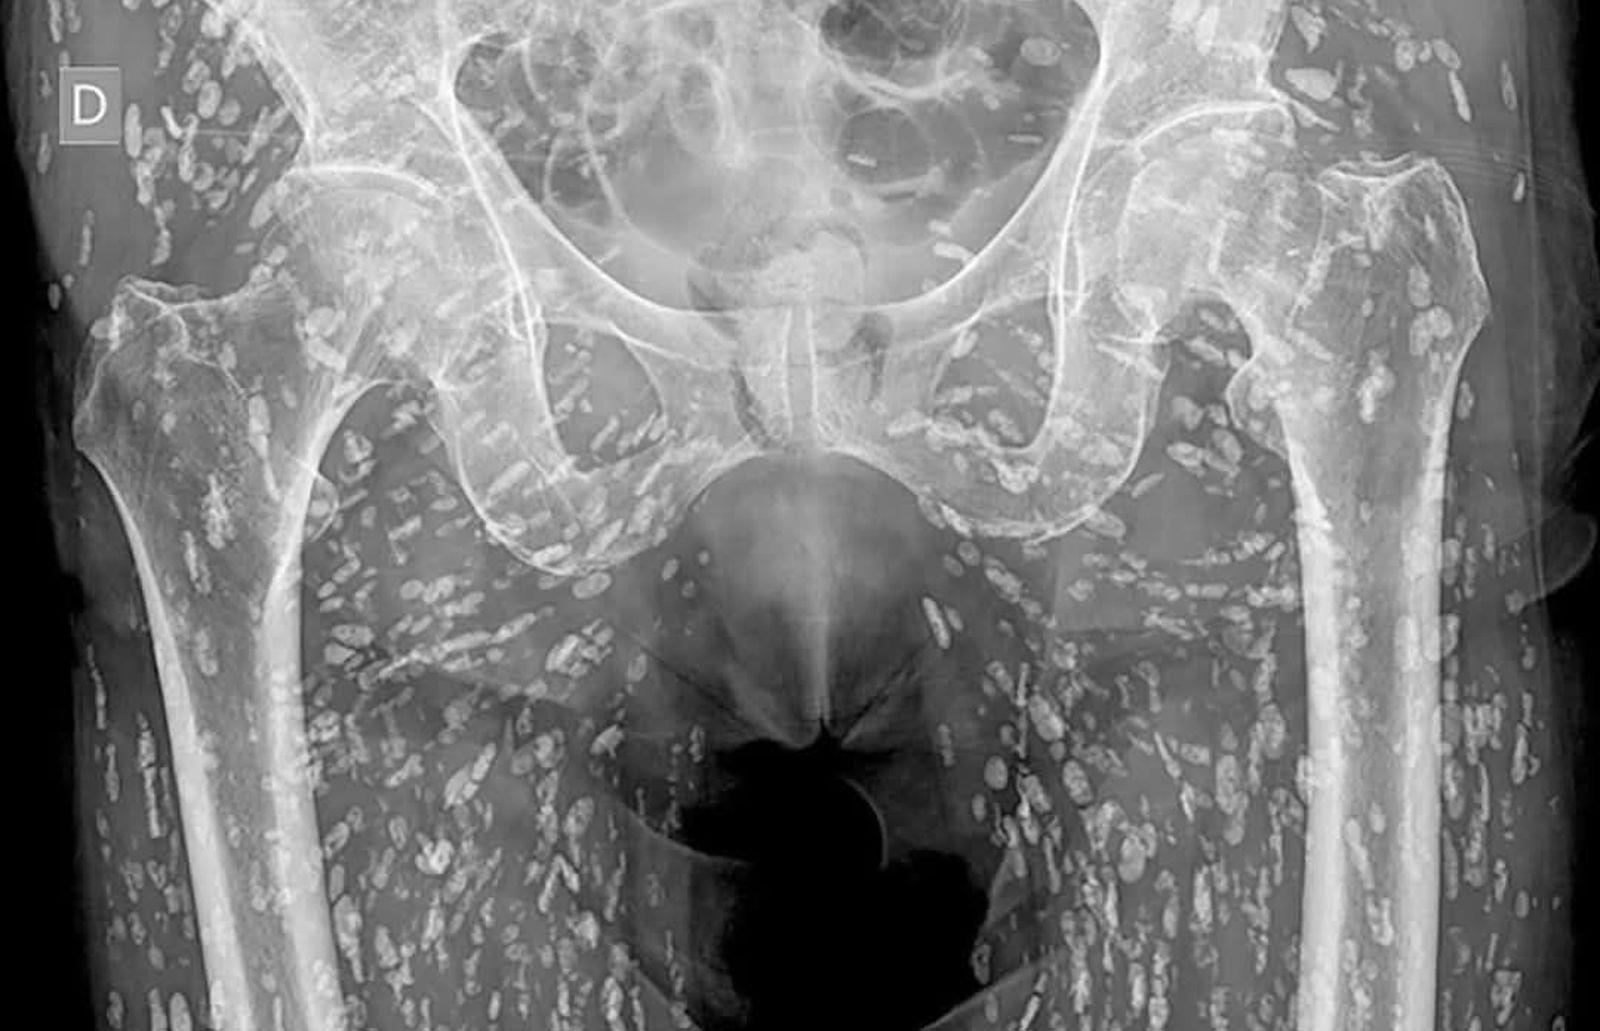

一名婦人照X片發現體內布滿大量寄生蟲。(圖/翻攝臉書粉專ไอ้แจ๋ว เมืองจันท์/鏡週刊)

泰國一名曾任職診所X光助理的網友分享了一段令人難忘的經歷,曾有一名阿嬤接受臀部到腿部的X光檢查,沒想到竟查出體內布滿寄生蟲,X光片上密密麻麻的白點讓醫護人員嚇到起雞皮疙瘩。

據泰媒《Khaosod》報導,這名婦人8年前接受X光檢查,影像結果卻顯示密密麻麻的白點,放射科醫生研判這些白點都是寄生蟲,布滿她的臀部到腿部,並強調這通常是長期食用生食和生肉所致,這番噁心的影像讓原PO感到十分毛骨悚然,甚至不斷用酒精清潔雙手。